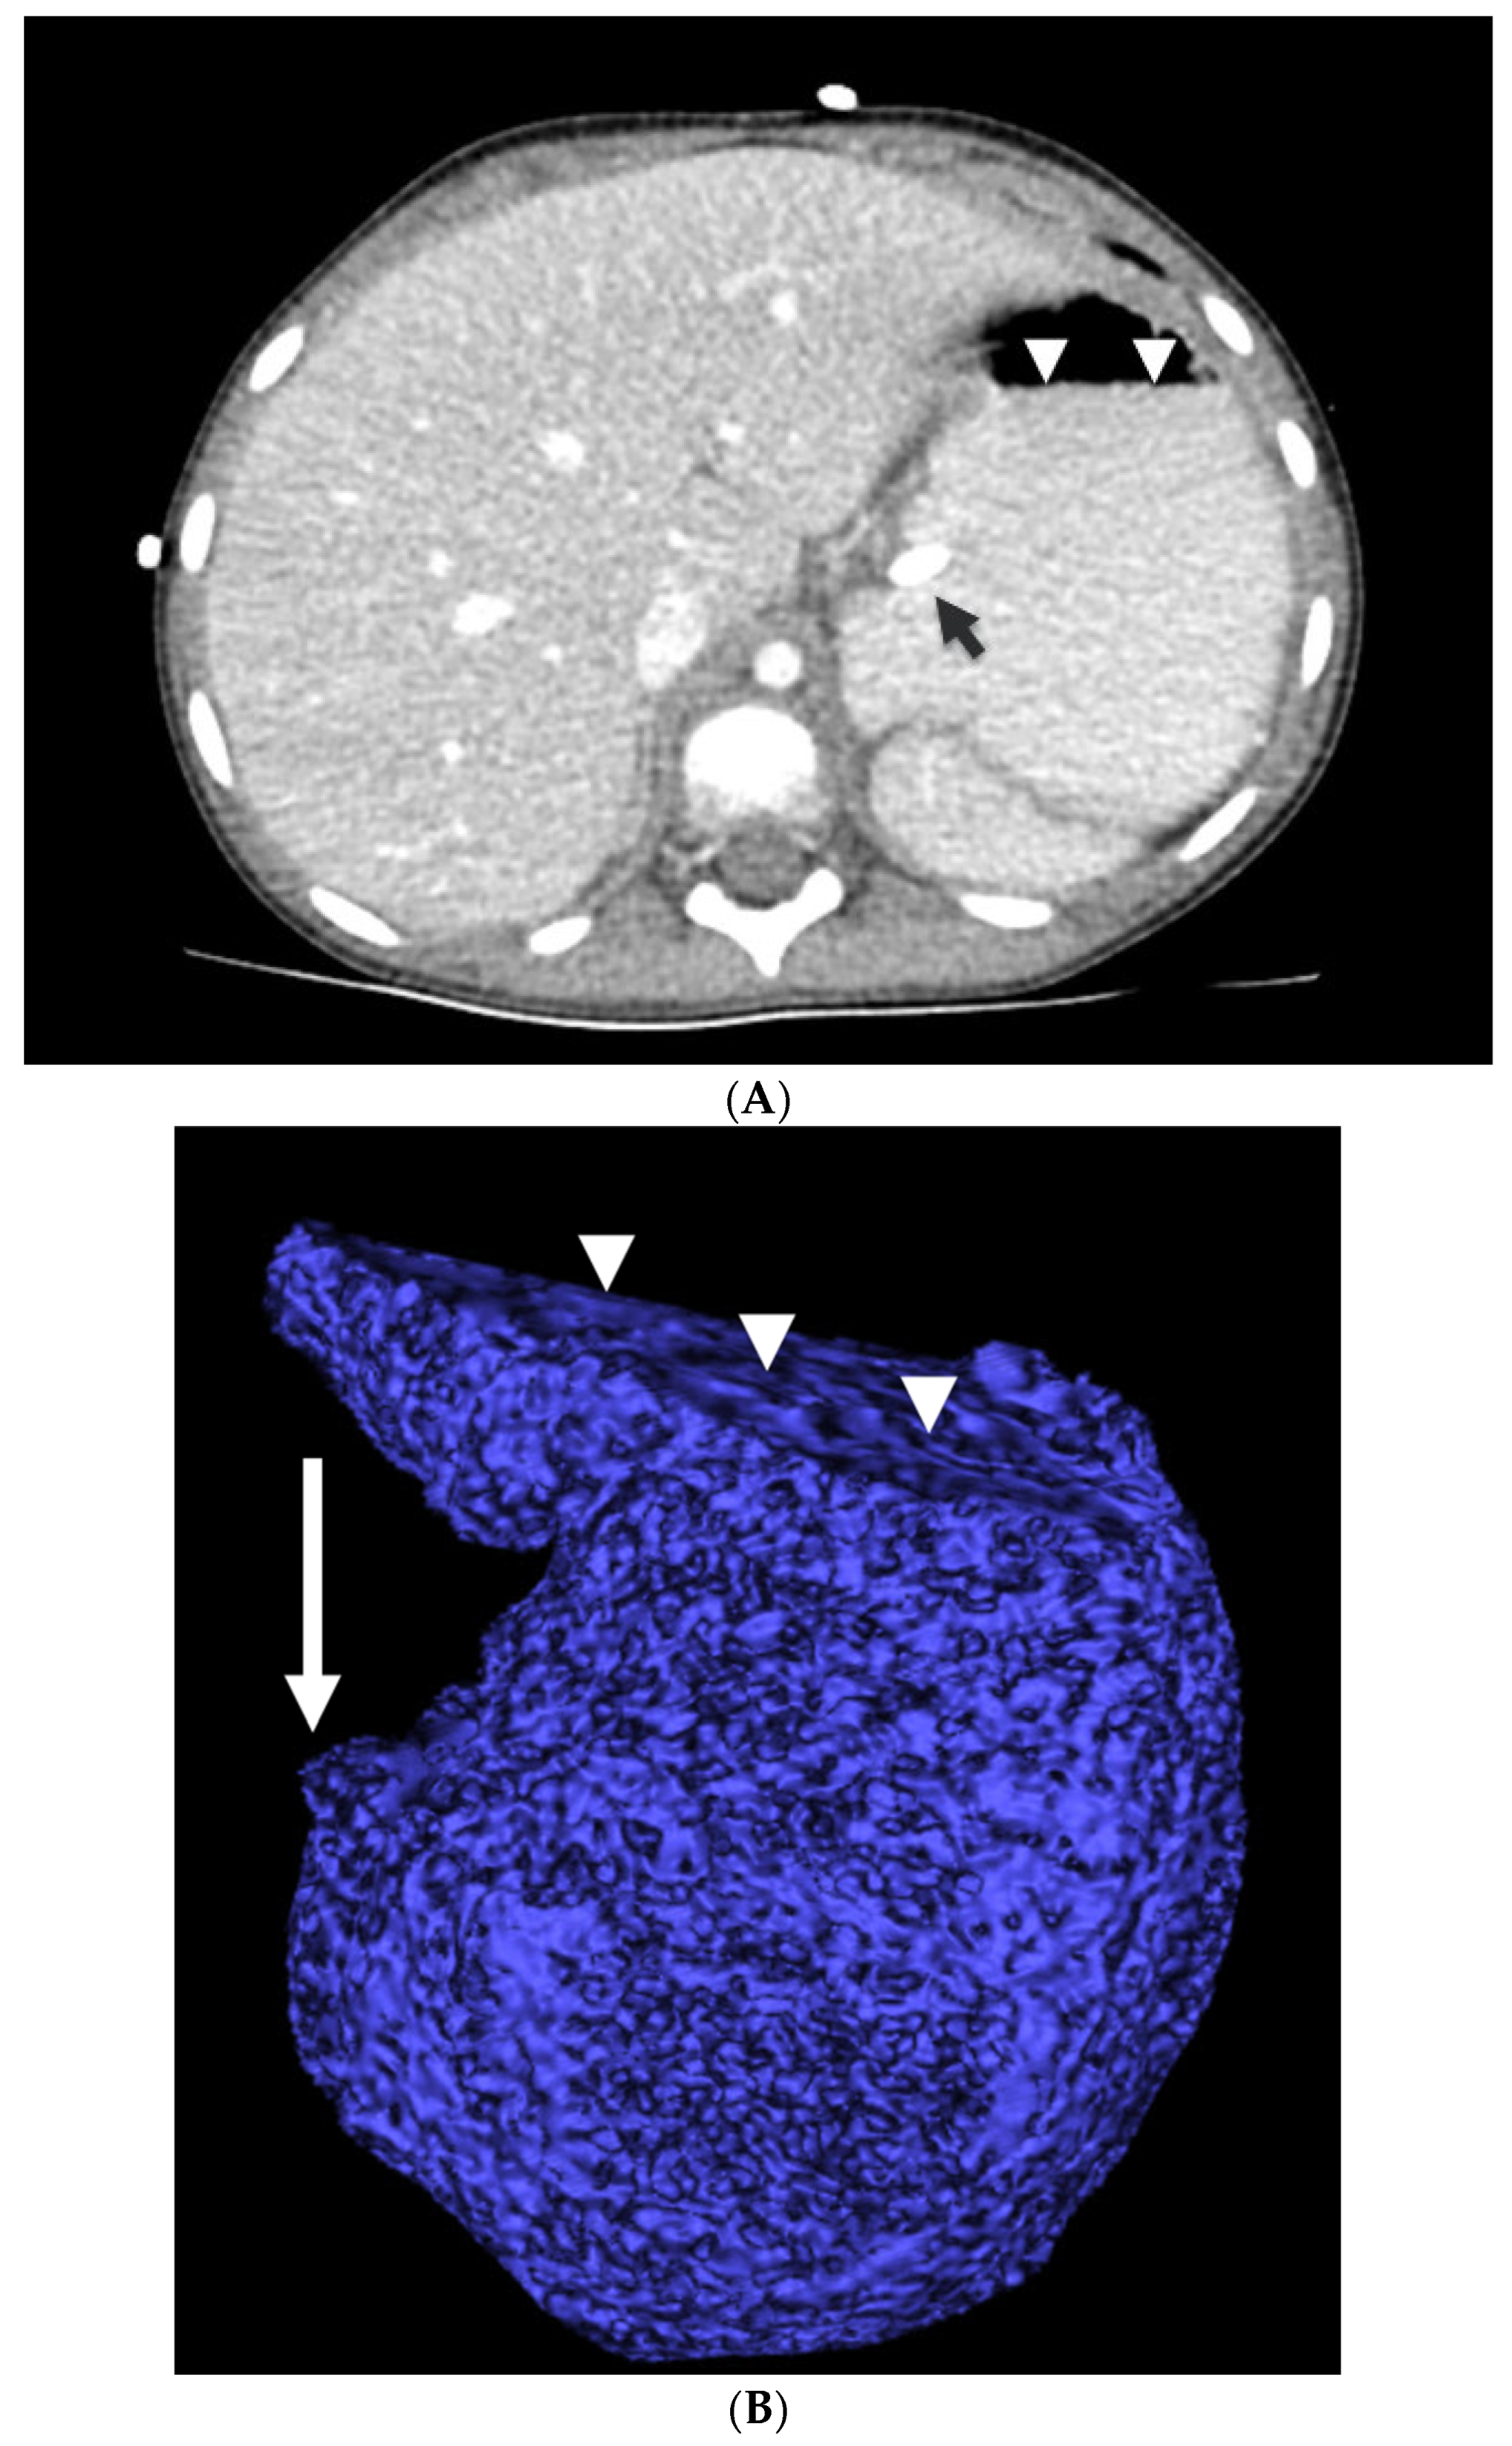

2.5. CT Image Evaluation